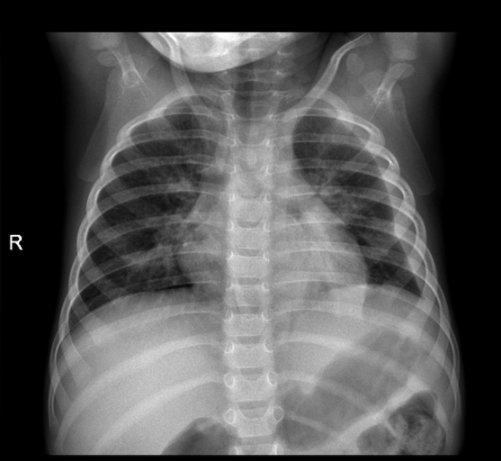

En la edad neonatal se realiza la radiografía anteroposterior (AP), y la posteroanterior (PA) en mayores de 2 años, reservando la proyección lateral para dudas razonables. Habitualmente, los estudios en niños colaboradores se realizan en bipedestación, mientras que en los más pequeños se realizan en decúbito supino. La ecografía no sería la primera técnica a realizar por sus limitaciones en un tejido ocupado por aire, y el TC sería excesivo, aún más en niños por su mayor sensibilidad a la radiación.